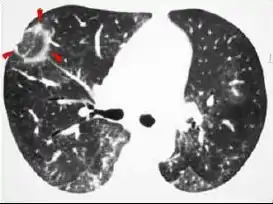

Симптом «матового скла» (англ. ground-glass opacity symptom) — неспецифічний радіологічний симптом, що відображає різні патологічні зміни в легеневій тканині на рівні альвеол при комп'ютерній томографії (КТ). Візуалізується як туманне, матове зниження прозорості легеневої тканини з диференційованим малюнком судин і бронхів на цьому тлі. Цей симптом може бути обумовлений частковим зниженням заповнення повітрям легеневих альвеол (транссудативної, ексудативної чи іншої природи), їх частковим спаданням (гіповентиляцією) або потовщенням їх стінок. Оскільки цей симптом є неспецифічним, може з'являтися при різних хворобах, під час постановки діагнозу слід враховувати анамнестичні дані, клінічні прояви і супутню патологію. У зв'язку з суб'єктивністю оцінки наявності симптому «матового скла», необхідно враховувати параметри сканування і візуалізації. Зокрема, занадто вузьке легеневе вікно створює «плямистість» зображення, що спотворює справжню картину, а низька роздільність і велика товщина зрізів (понад 4 мм) створюють ефект усереднення, скрадає і розмиває дрібні деталі.

Симптом «матового скла» може відзначатися навколо вогнищ ущільнення легеневої тканини («симптом ореолу»). Такі зміни вперше були описані та вважається типовими для раннього інвазивного аспергільозу легень, хоча і не є досить специфічні. Виявлені випадки появи симптому ореолу навколо вогнищ, що виникають при інших інфекційних хворобах, злоякісних ураженнях легень. Подібні зміни можуть спостерігатися навколо «псевдовогнищ» після біопсії легені.